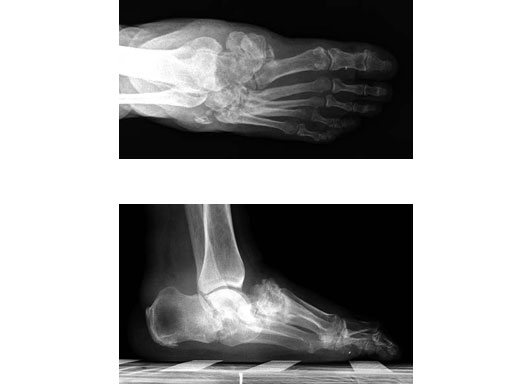

Case 2: 48-year-old male

Case provided by Andrew K Sands, New York, USA

Charcot foot treated with MFB and X-plate.